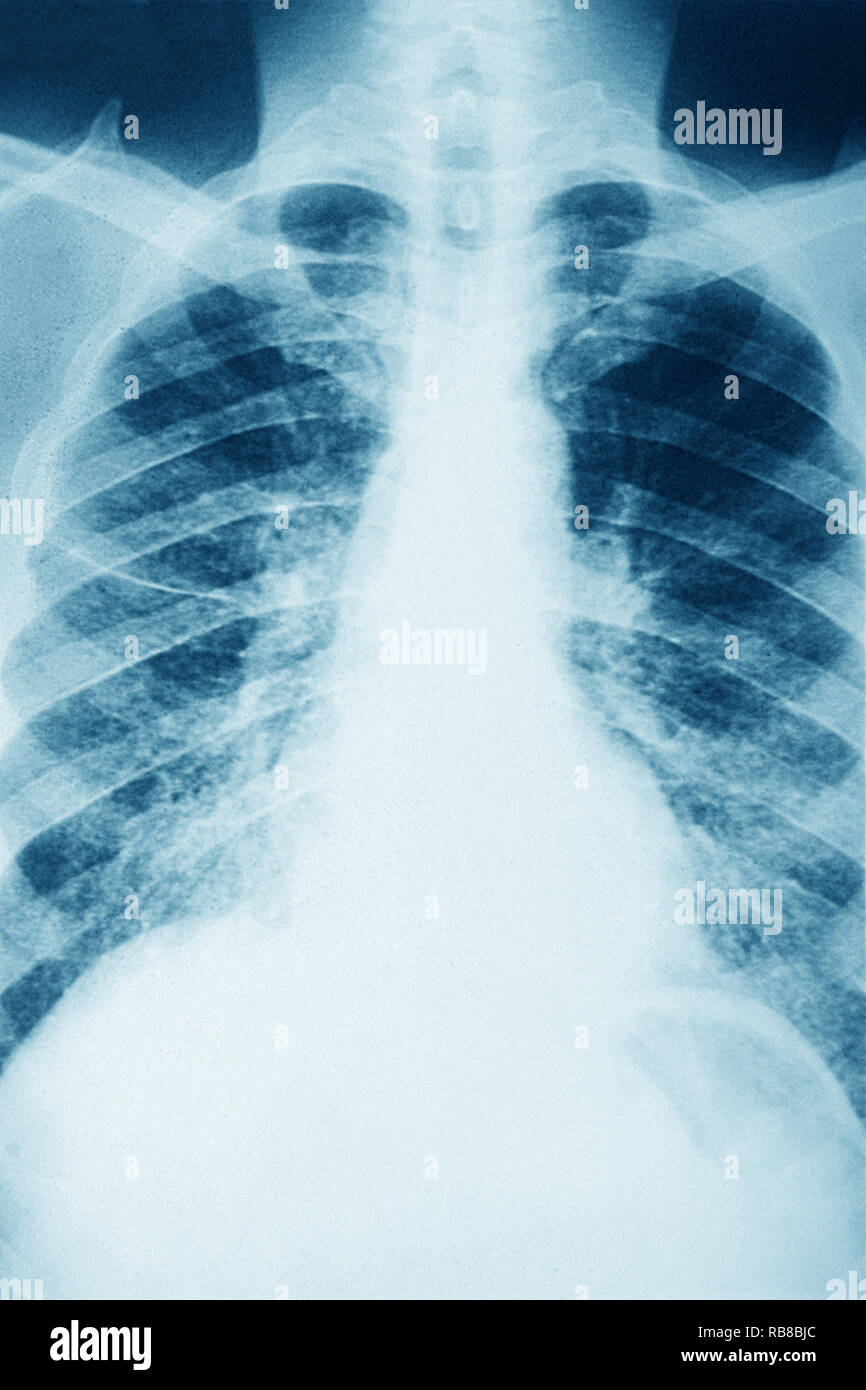

From www.sciencephoto.com

Pulmonary sarcoidosis, Xray Stock Image M260/0310 Science Photo Sarcoidosis X Ray Images sarcoidosis can involve all of the organ systems of the body, but thoracic lymph nodes and the lung parenchyma are most often and most visibly. Pulmonary fibrotic changes may also. this review explores some of the key concepts in the imaging of pulmonary sarcoidosis: abnormalities may be seen on chest radiographs in more than 90% of patients. Sarcoidosis X Ray Images.